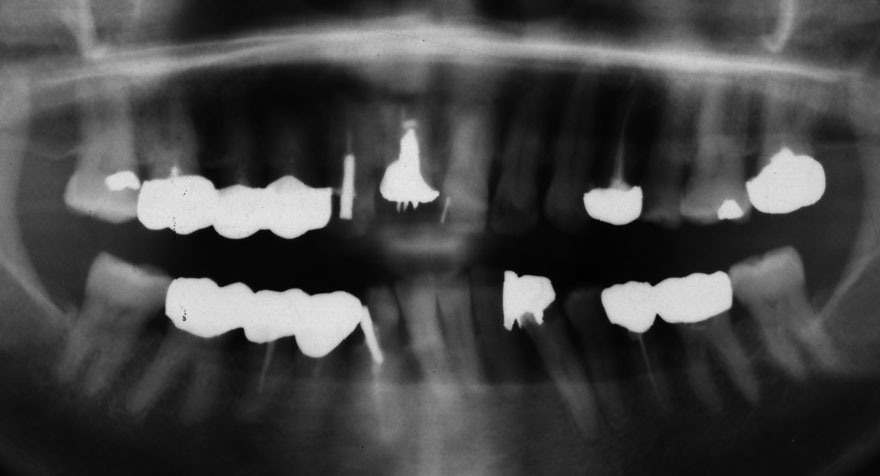

初診時 50歳 女性

22年後 72歳